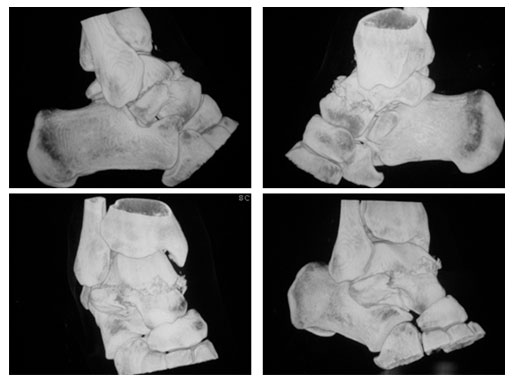

23-year-old male with moto cross accident

Case provided by P. Cronier, Angers, France

ORIF (day 5): Anteromedial approch and Ollier approach